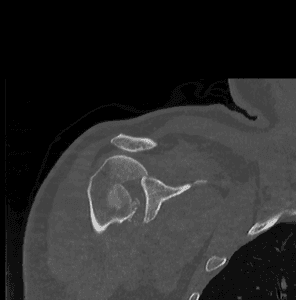

- Imaging:

- X-rays: Standard views to assess the fracture and dislocation.

- CT Scans: For detailed images.

- CT Angiography: Useful for identifying vascular structures in certain fracturepatterns.